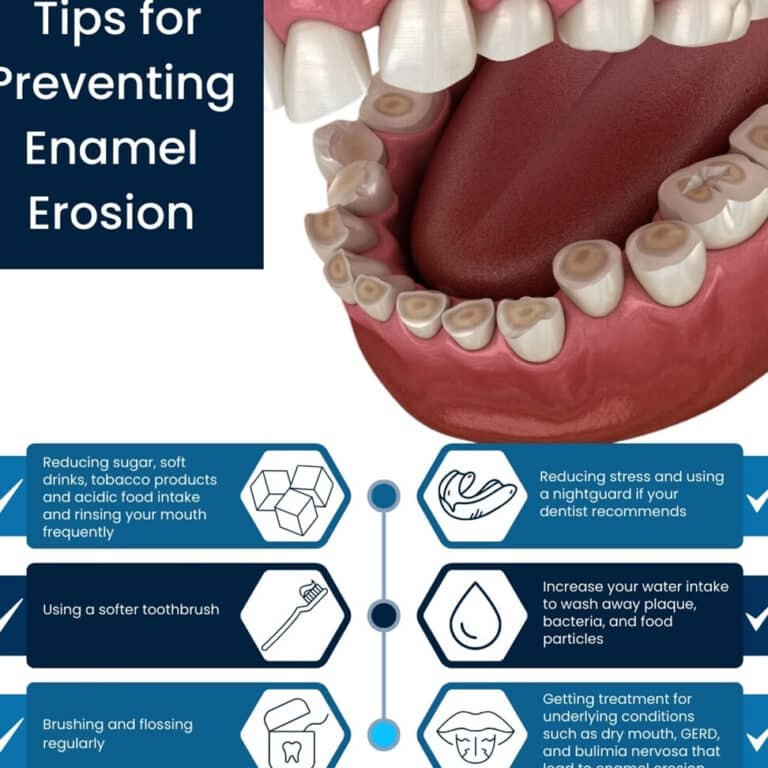

La pérdida o deterioro del esmalte dental es un problema común que afecta la salud bucal, pero...